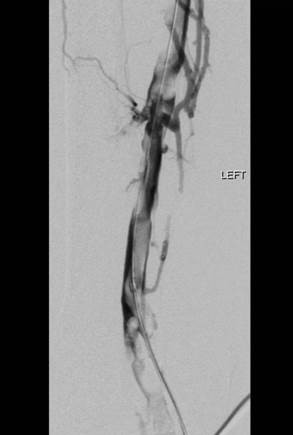

Venograma de la pierna izquierda donde se muestra un trombo oclusivo en las venas profundas más visualizadas.